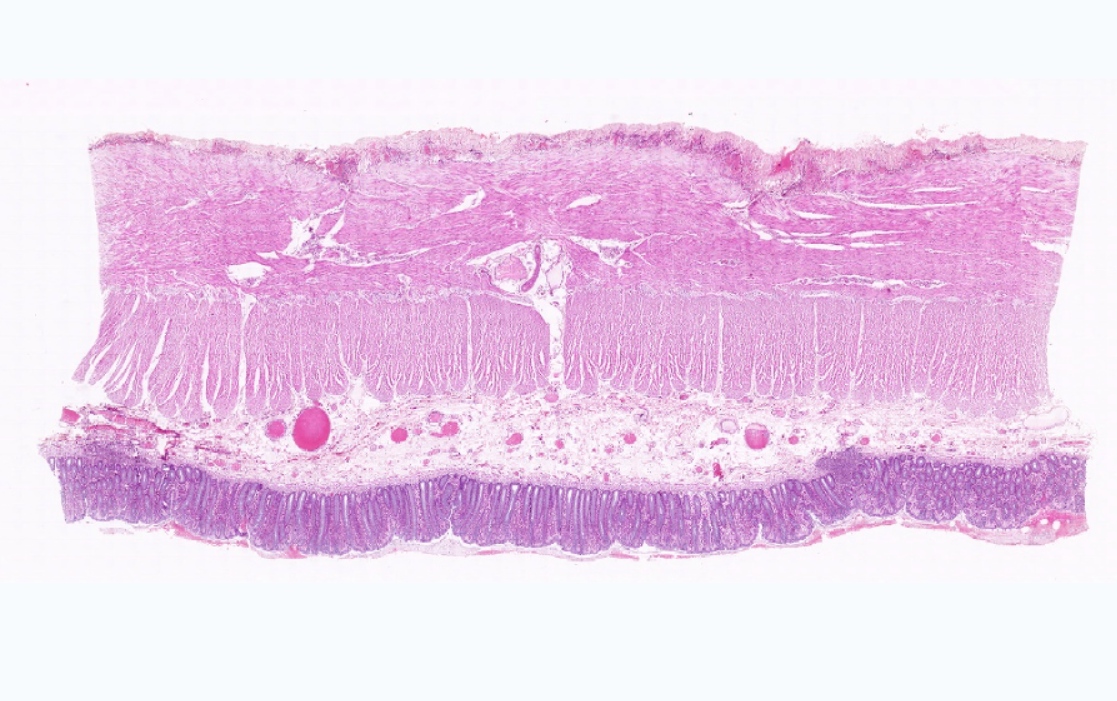

2.结肠腺

3.黏膜下层

4.外膜